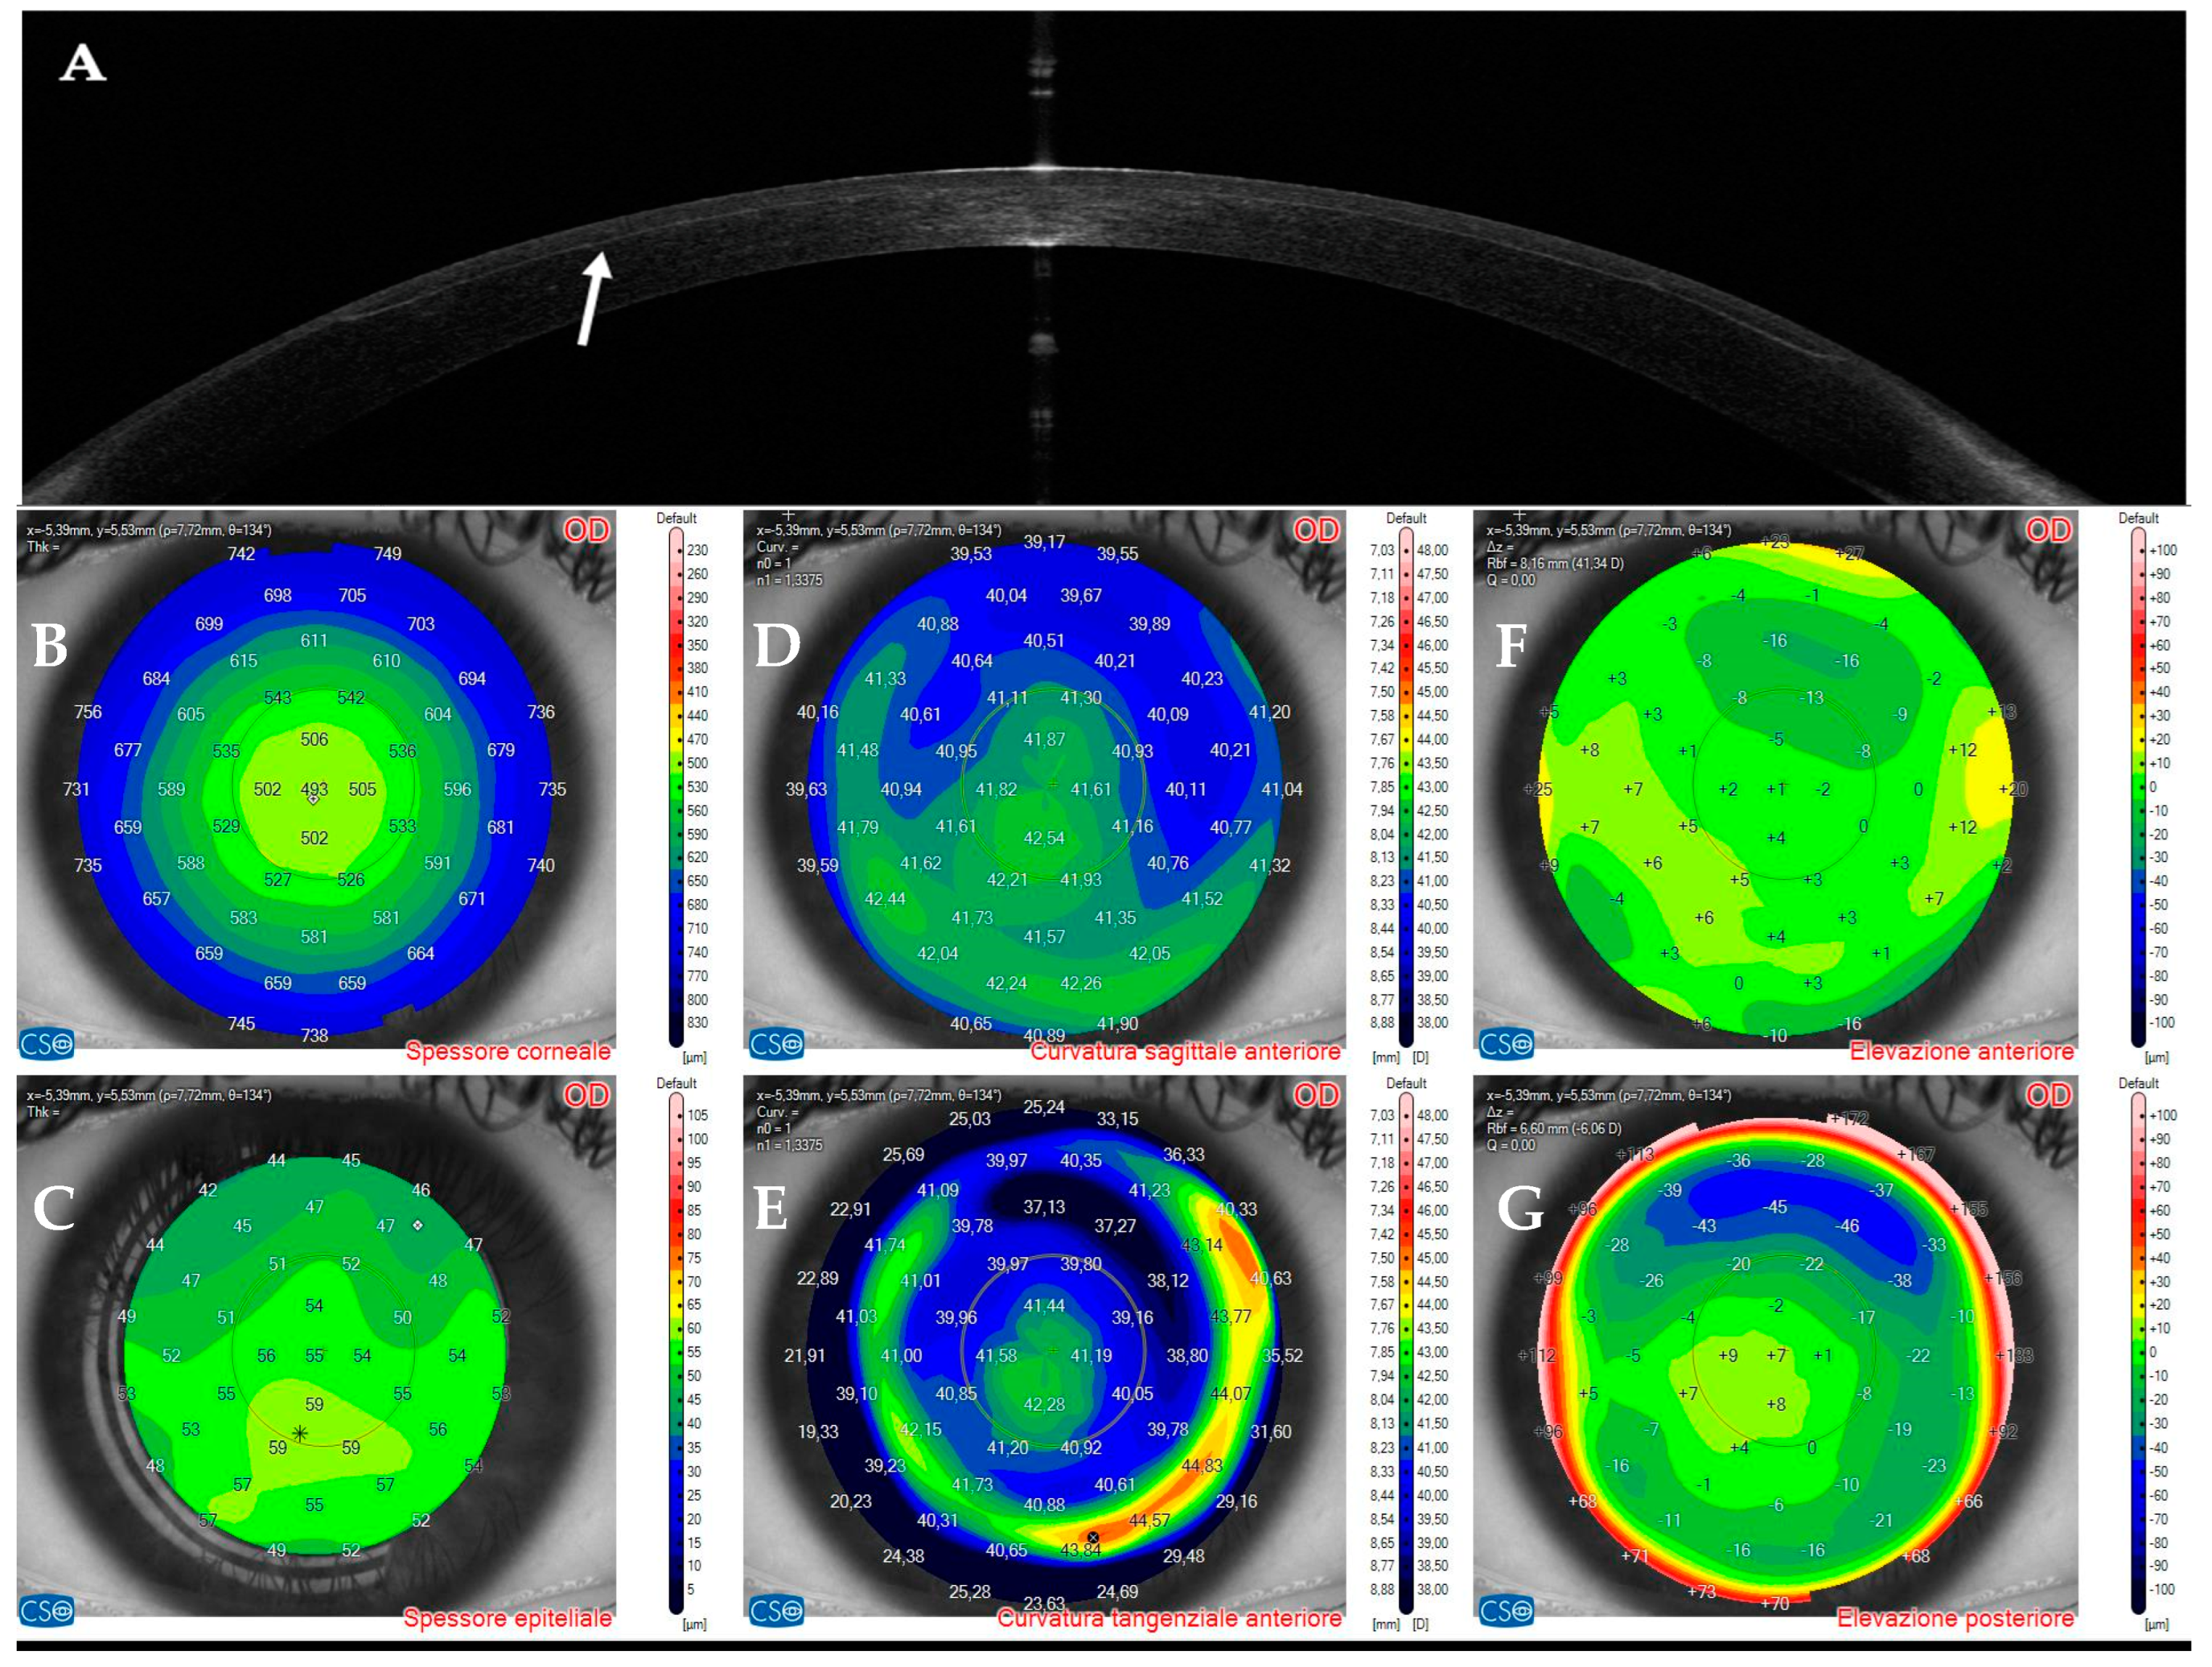

3.3. Patient #3